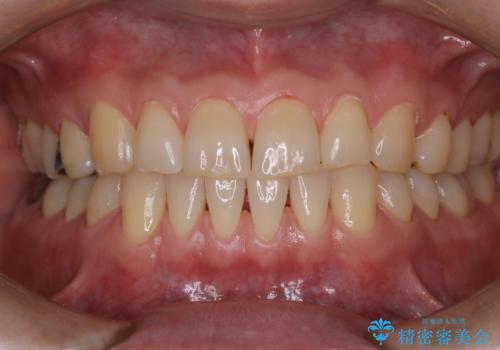

タバコとコーヒーによる頑固な着色落とし

- 毎日の喫煙とコーヒーを飲むことにより、ひどく着色がついてしまったとのことです。PMTC60分コースを行いました。

PMTC(保険外治療)は、毎日の歯磨きで落としきれない汚れや、コーヒ、紅茶・タバコのヤニなどの着色も除去します。目には見えない歯と歯の間・歯肉の境目などに残っているプラーク(歯垢)もしっかり取り除きます。PMTCでは専門的な機械や材料を使用して、徹底的に汚れを除去するため、虫歯・歯周病・口臭予防などにつながります。

また、仕上げのトリートメントでは歯の表面の凸凹にミネラルを補給して、ツルツルの表面に仕上げます。定期的にPMTCを行うことにより、歯質の強化になり着色がつきにくい状態になります。